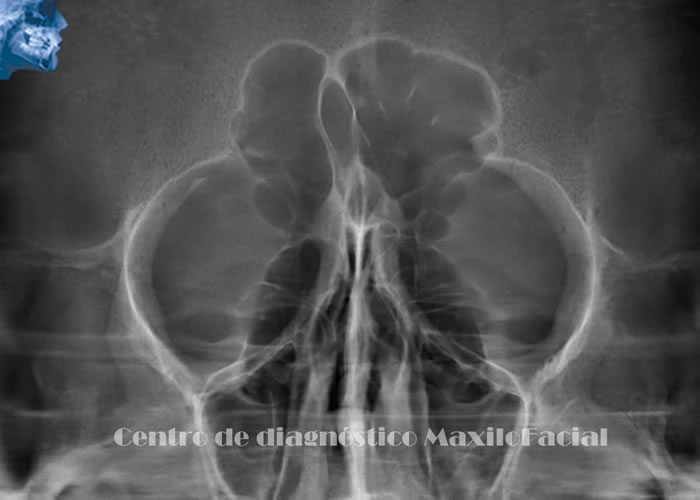

Otras Técnicas Radiográficas Dentales

Ofrecen una visión complementaria para evaluar senos maxilares, fracturas de cóndilos, asimetrías faciales, etc. Dependiendo de la zona de interés.

A continuación queremos mostrarle nuestra galería con algunas imágenes de casos llegados a Cedimax - Centro de Diagnóstico Maxilofacial, si requiriera más ejemplos de casos no dude en contactarse con nosotros.